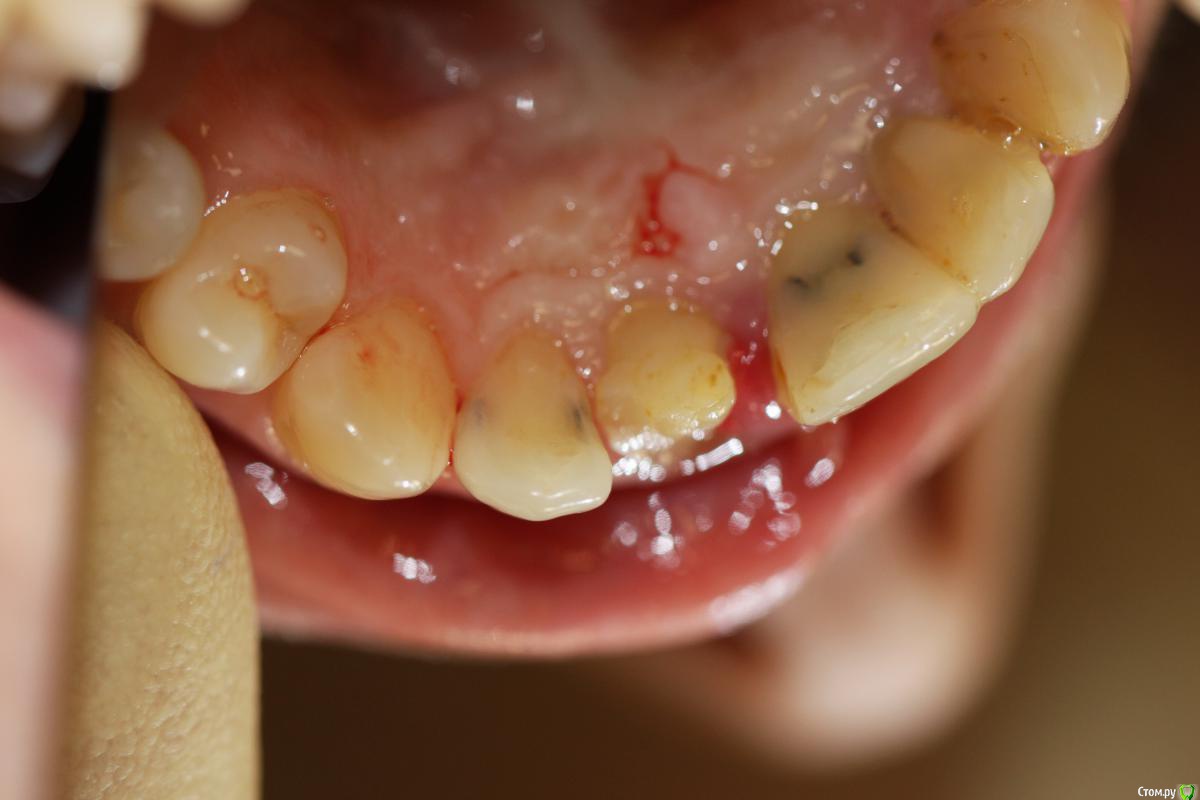

skeettrap Опубликовано 19 марта, 2016 Поделиться Опубликовано 19 марта, 2016 Работа из категории - для души. Попутно сделан кариес у 12 с медиальной стенки , 21 - только подполирована медиальная стенка. 3 Ссылка на комментарий

krokomot Опубликовано 19 марта, 2016 Поделиться Опубликовано 19 марта, 2016 Для бюджета, очень даже не плохо, учитывая общую ситуацию во рту. В посте не хватает кадрирования фотографий ( выровнять, обрезать), ну конечно рентгеновского снимка. Ссылка на комментарий

dok1 Опубликовано 20 марта, 2016 Поделиться Опубликовано 20 марта, 2016 Зуб ушёл ниже десны. Это сто проц. удаление, имплант и коронка. По мне так пациент переплатил. К импланту всё равно придёт. Ссылка на комментарий

krokomot Опубликовано 20 марта, 2016 Поделиться Опубликовано 20 марта, 2016 Зуб ушёл ниже десны. Это сто проц. удаление, имплант и коронка. По мне так пациент переплатил. К импланту всё равно придёт.Что ж вы все зубы что ушли под десну удаляете? Или вы про удлинение клинической коронки забыли или экструзию? 1 Ссылка на комментарий